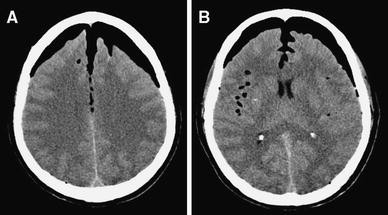

Review Of The Management Of Pneumocephalus Surgical Neurology International

surgicalneurologyint.com